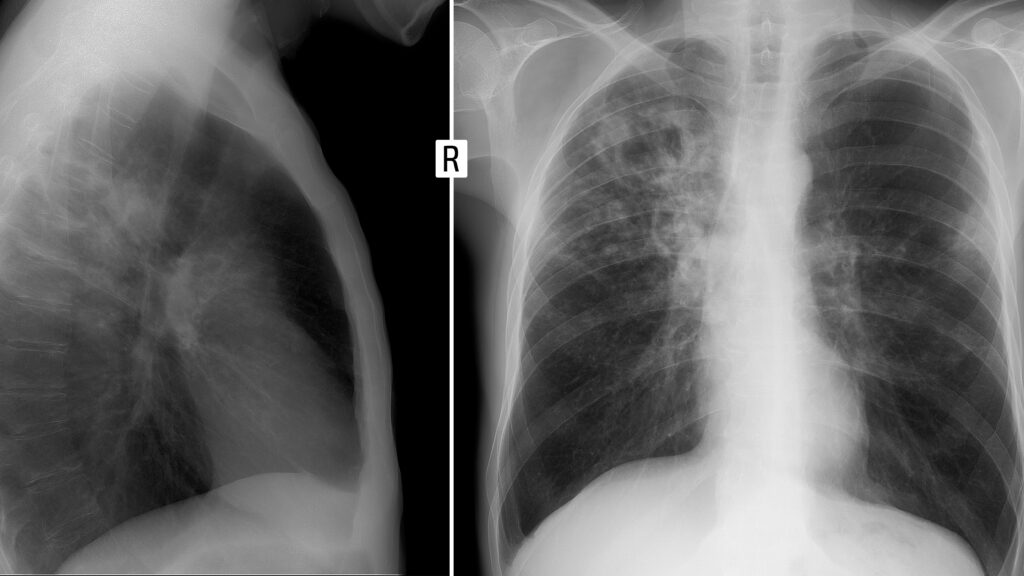

CHICAGO — In front of a room of radiologists, Warren Gefter pulled up a chest X-ray on a large screen. It looked like a standard, uncomplicated read. Heart: normal. Lungs: clear.

But Gefter, a professor of radiology at Penn Medicine, wasn’t looking to his peers to interpret the scan. Instead, he highlighted what a generative artificial intelligence model had put in its written findings, along with those normal results: “Left hip prosthesis in situ.”

“Clearly, a nonsensical hallucination,” said Gefter. Chest X-rays cut off at the bottom of the rib cage, with the hip far out of sight: The AI had made up an artificial hip joint.